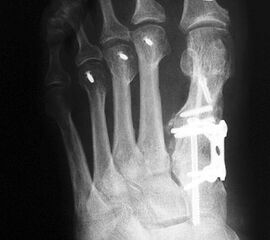

Die dorsoplantaren Röntgenaufnahmen zeigen eine Open-wedge Technik mit der normalerweise ein erhöhter intermetatarsaler Winkel gut zu korrigieren ist (Abbildung 3). Die Wirksamkeit einer Basisosteotomie ist umso größer, je proximaler diese durchgeführt wird. Je weiter distal die Osteotomie, umso geringer die Korrektur. Auf den postoperativen Bildern ist der distal unverändert große Abstand zwischen Metatarsale I und Metatarsale II erkennbar, bei gleichzeitiger Subluxation des Großzehengrundgelenks und dezentrierten Sesambeinen. Darüber hinaus finden sich initiale degenerative Veränderungen im Großzehengrundgelenk. Klinisch bestand eine hohe Weichteilspannung, bei verkürzter Extensor- und Flexor hallucis longus Sehne.  Daher wurde ein verkürzendes Verfahren zur Revision gewählt (Abbildung 4). Die Lapidusarthrodese stellt ein sehr zuverlässiges Verfahren zur Behandlung von Hallux valgus Rezidiven dar 9. Die Fusion des Tarsometatarsale-I-Gelenks kombiniert Stabilität mit einem hohen Korrekturpotenzial. Aufgrund der verfahrensimmanenten Verkürzung des ersten Strahls und der in diesem Fall bereits präoperativ vorhandenen Transfermetatarsalgie wurde die Entscheidung für eine verkürzte Weil-Osteotomie am zweiten bis fünften Strahl gefällt. Die Kombination beider Verfahren führte zu einem homogenen Metatarsale-Index und zu einer gleichmäßigen plantaren Druckverteilung 10. Die Hallux valgus interphalangeus Fehlstellung wurde mit einer Akin-Osteotomie korrigiert.